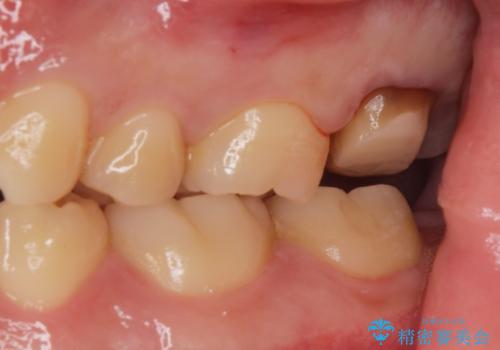

- 銀歯を良いものに変えたいとの事で来院。

過去に根の治療もされている歯だが土台が粗造なため根の治療からやり直しを行いゴールドクラウンにて治療を行いました。

また手前のはに虫歯があったためセラミックの詰め物で治療しました。

適合の良い被せ物が入りました。

ゴールドの被せ物は適合がよく虫歯の再発のリスクが低くなります。